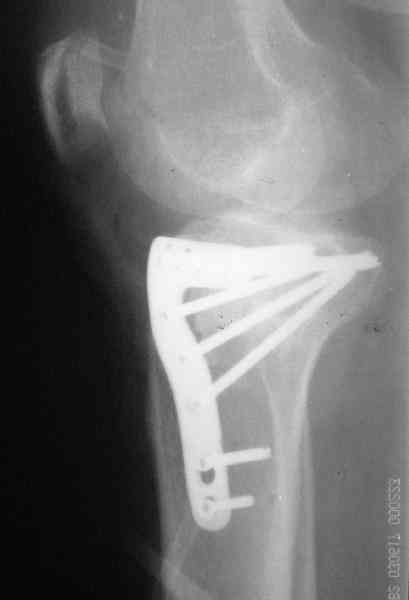

Уважаемый Абдурашид. Если нет противопоказаний , то из оперативных способов, я бы рекомендовал следующие: Полное замещение наружного мыщелка аллотрансплантатом либо открытая репозиция с элевацией и замещение дефекта ауто или аллокостью. В Ваших условиях , я бы рекомендовал второй способ. Во-время элевации необходимо разъединить фрагменты со стороны сустава ( надсечь скальпелем по линиям перелома, а затем тонким остеотомом их разъединить. При помощи долота произвести неполную остеотомию ( захватите не менее 1,5 - 2 см губчатой кости и поднять фрагменты, визуально отрепонировать и фиксировать 2-3 спицами. Дефект заместить костным ауто или аллатрансплантатом. Окончательная стабилизация пластиной ( лучше с угловой стабильностью, либо АВФ - позволит спокойно устранить угловую деформацию.

Недавно поступила больная через 1,5- 2 месяца.